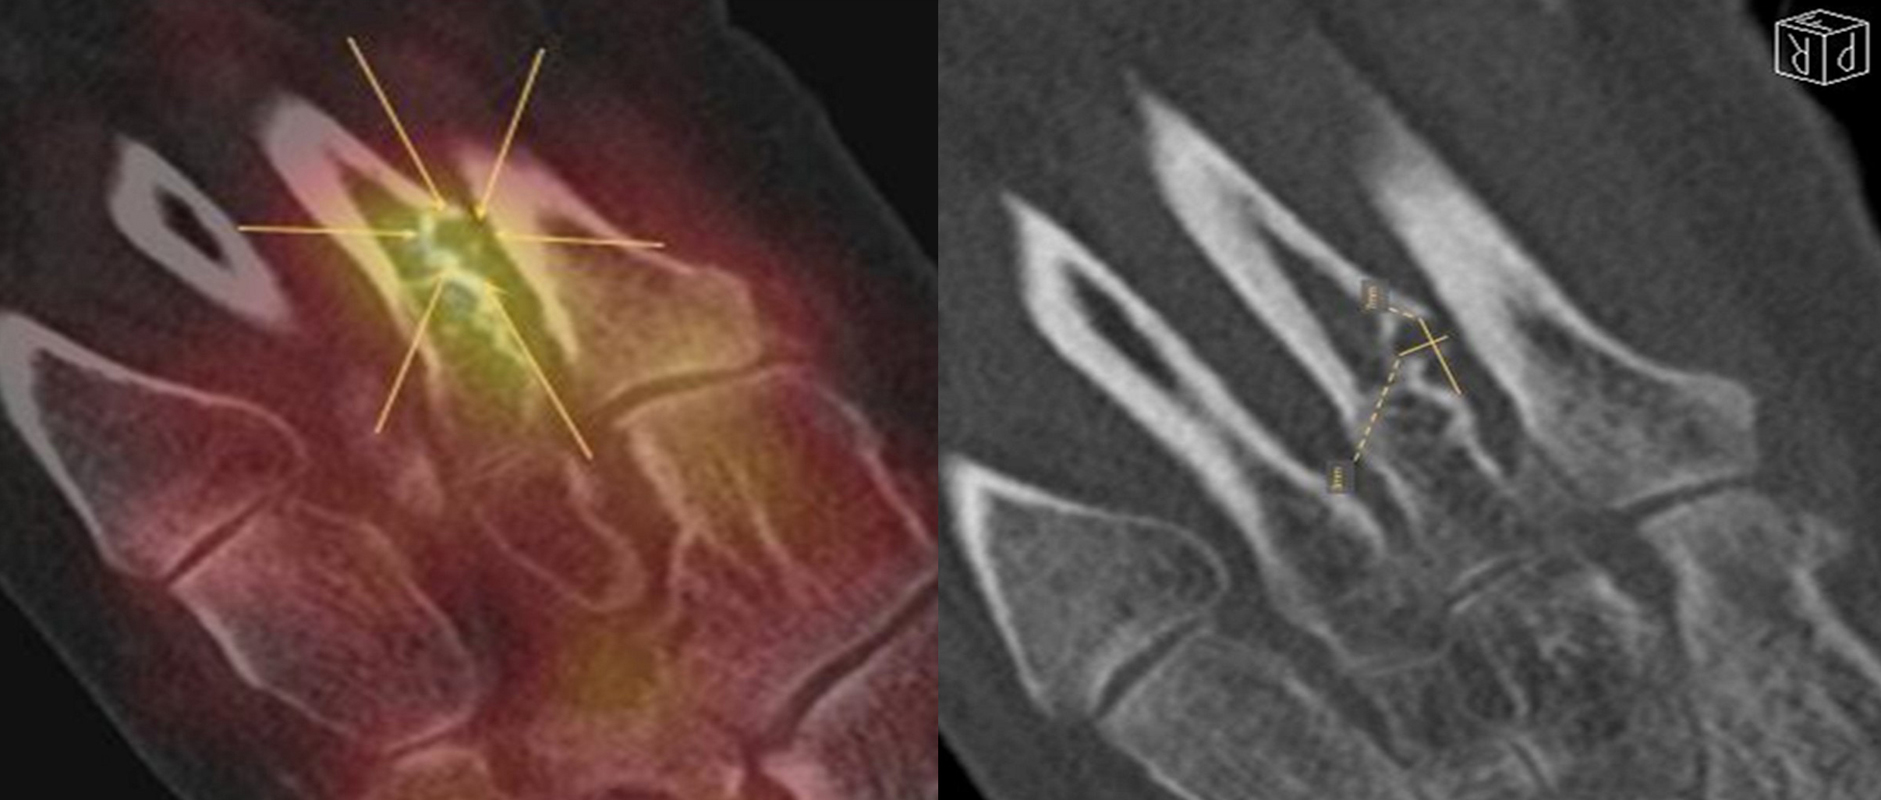

Coalitionen können auf Röntgenbildern wegen überlappender Strukturen häufig nicht sicher diagnostiziert werden, so dass MRT und/oder CT erforderlich sind, um eine Coalitio eindeutig nachzuweisen. Der Vorteil der SPECT/CT liegt darin, dass neben der submilimeter-genauen Darstellung der Anatomie, womit die charakterischten Röntgenzeichen einer Coalitio erkannt werden, auch die Stressreaktion bzw. die Scherkräfte, die auf die Syndesmose oder Synchondrose wirken, sichtbar gemacht werden können. Dabei hat die SPECT/CT eine deutlich höhere Treffsicherheit als die MRT zur exakten Lokalisation der Stressreaktion 44.

Abbildung 4.1.zeigt das Beispiel einer Patientin mit einer Stressreaktion zwischen Processus anterior calcanei und Os naviculare, welche einer fibrösen symptomatischen Coalitio entspricht, die primär in der Bildgebung (Röntgen, MRT) nicht erkannt wurde. Bei Knick-Senk-Fuß erfolgte zunächst eine Talo-Naviculare Arthrodese. Postoperativ nahmen die Schmerzen zu. Anstelle eines SPECT/CT erhielt die Patientin zwei Serien einer Röntgen-Reiz-Bestrahlung. Die Patientin stellte sich in einer auf Fußerkrankungen spezialisierten Klinik vor, die die Patientin zur weiteren Abklärung zu uns überwies. Erst die Abklärung mittels SPECT/CT zeigte die eine fibröse Coalitio zwischen Processus anterior calcanei und Os naviculare bei vollständig reizlos durchbauter Talo-Navicularer Arthodese. Es wurde daraufhin eine erfolgreiche konservative Therapie u. a. mittels gezielten Injektionen und Stosswellen eingeleitet.

Die Abbildungen 4.2.a bis d zeigen den typischen Aspekt einer talacalcanearen Coalitio. Es besteht nur eine linksseitige, symptomatische Coalitio talocalcaneare (4.2.a und c); das 35 Tage zuvor angefertigte MRT zeigt keine auffälligen Signalveränderungen (4.2.b und d).

Abbildung 4.3. zeigt die Ursache für rechtsseitige Sprunggelenksbeschwerden bei einem Patienten mit talocalcanearen Coalitionen: nur die osteochondrale Läsion an der distalen rechten Tibia ist die Ursache des Schmerzes. Die bilateralen talocalcanearen Coalitionen sind asymptomatisch.